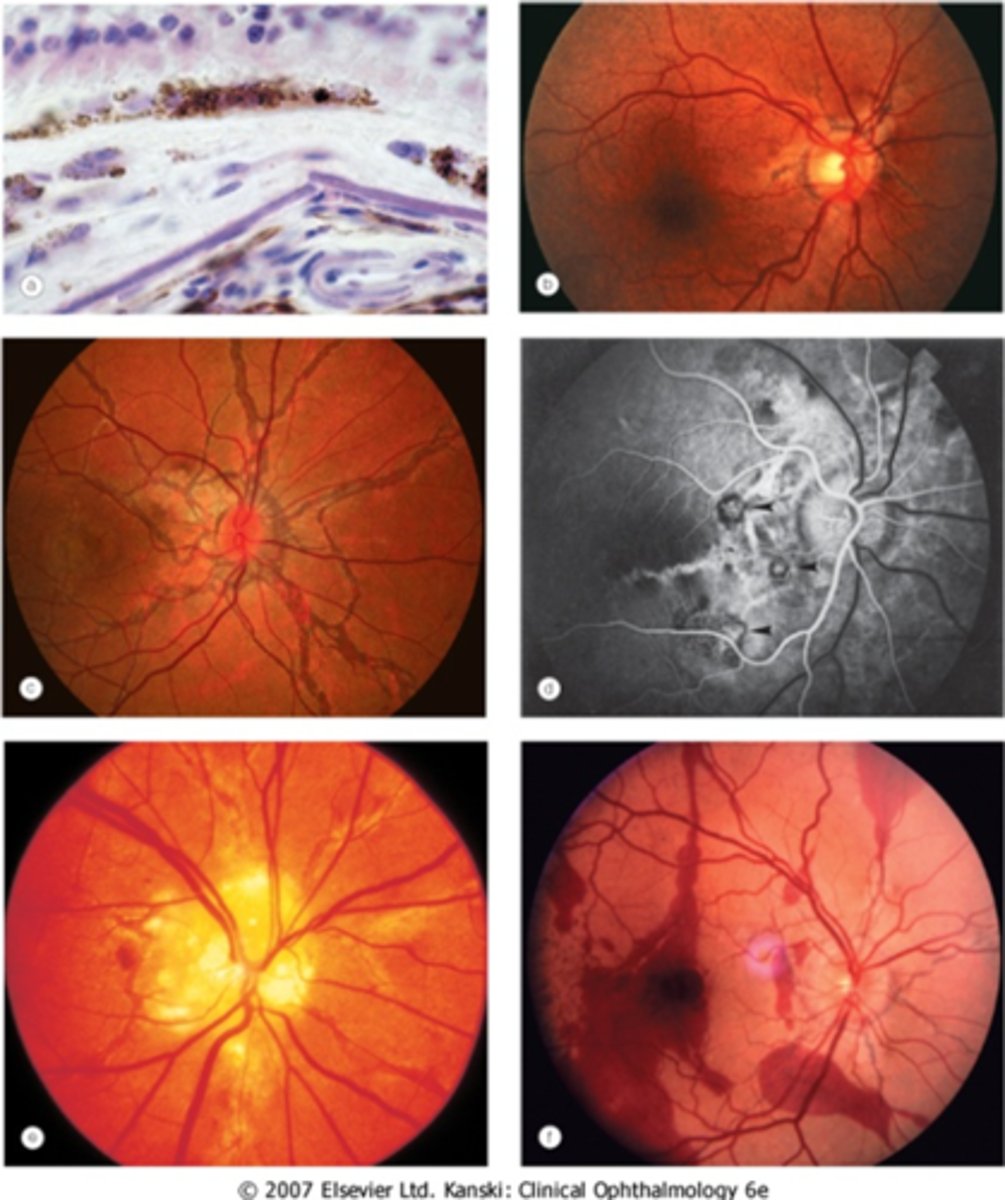

What finding of toxoplasmosis is seen in A/B?

retinitis turns into hazy scar with nerve pallor

What finding of toxoplasmosis is seen in C/D?

scarring overtime with VA loss/scotoma

What is seen in toxoplasmosis with OCT?

acute = retinitis = inflam, thickening of layers

acute = vitritis = dots and haze vitreous

chronic = necrotizing atrophy = scarring, thinning

What findings of toxoplasmosis are seen here?

retinal vasculitis

exudative scar

focal, hazy vitritis and retinitis

What findings of toxoplasmosis are seen here?

latent scars